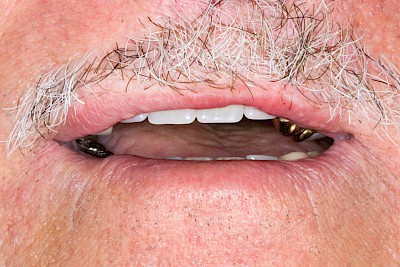

Totalprothese

Werden alle Zähne mit einer Zahnprothese ersetzt, spricht man von Vollprothesen oder Totalprothesen ("Die Dritten"). Diese bestehen häufig aus zahn- und rosafarbenem Kunststoff. Metallgitter oder Metallbügel bzw. Abdeckungen im Gaumenbereich aus Metall dienen mitunter der besseren Stabilisierung der Gesamtkonstruktion, z. B. weil Menschen Knirschen und Pressen.

Manchmal sieht eine Zahnprothese von außen aus wie eine Totalprothese: kein eigener Zahn und trotzdem sind darunter noch Zähne "versteckt" ggf. sogar mit Riegeln, die zuerst geöffnet werden müssen, um die Prothese herausnehmen zu können. Man spricht in diesen Fällen von einer Cover-Denture (Zahnbedeckende Prothese). Eine Zahnprothese, die man noch nicht kennt, sollte deshalb immer senkrecht abgenommen werden. Kippende Bewegungen können noch vorhandene Zähne verletzen bzw. beschädigen oder abbrechen.

Beispiele 33 Bilder